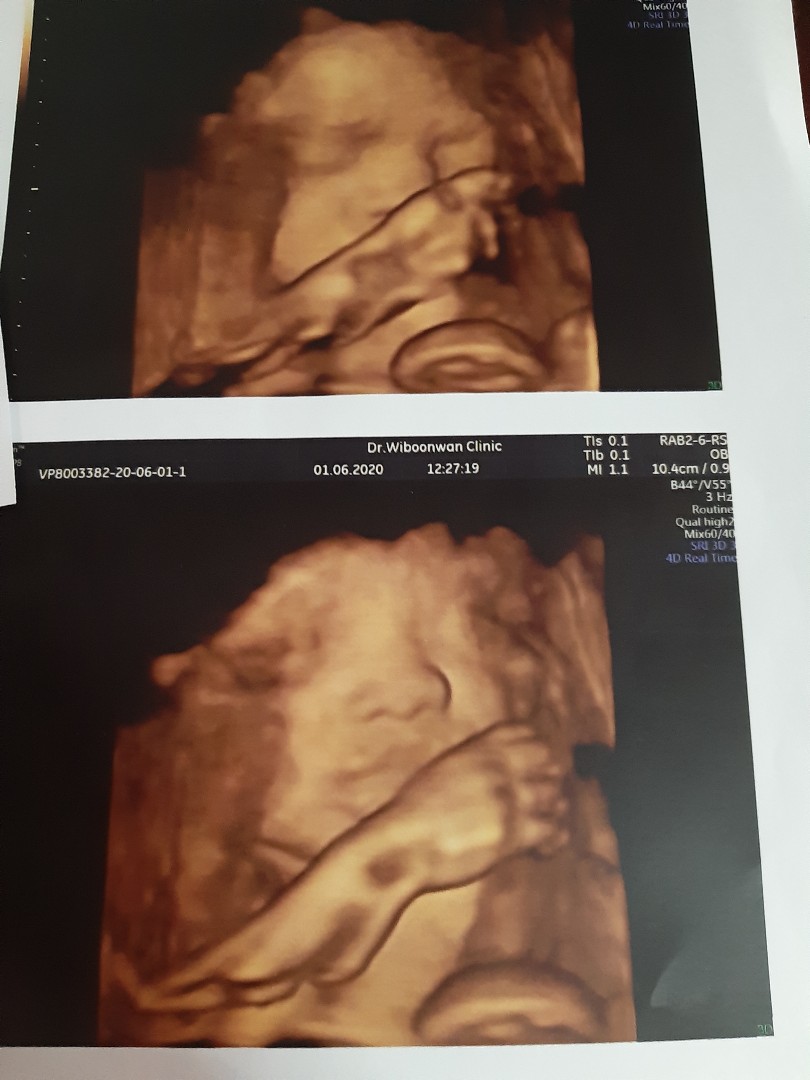

เห็นหน้าชัดกันมั๊ยคะ บ้านนี้ เอามือบังตลอดเลยค่า หมอเขย่าท้องก็แล้วไม่เอาออกเลยย ??

33 วีค

29weekคะ

28wค่ะ

34วีก

34+6